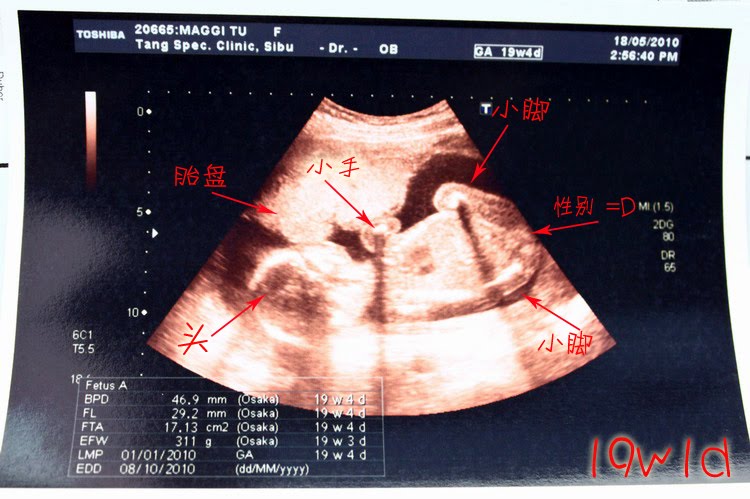

原来还是我多心了,在B超下的点点一直都在肚子里活泼的动

手啊脚啊,没有一刻是停下来的~

点点真的长大了很多!普通的2D超音波都能清楚得看到点点的体型

医生也非常确定的再一次确定了宝贝的性别,这次dear也听到了哦。

问了最担心的宝宝发育问题,医生回答说:

好好的,健康,没有兔唇。啊~~~~安心!!!=)

看看长大不少的点点^^

这孩子和上个月产检一样,可真一点也不害臊!

那双脚开到比谁都大!一眼就看出来那可爱的性别(保密)~

而且还面向我们呢 =)

♥点点的B超报告单数据显示♥胎头双顶径(BPD) 46.9mm,股骨长(FL) 29.2mm

,躯干横断面积(FTA) 17.13cm2

胎儿体重(EFW) 约311g

我本身的宫高 19cm

看吧!双脚真的开很大 =='''

点点可爱的头骨和脊椎骨~

最期待的4维B超时刻!点点小宝贝的整体~

(胎盘在前面,遮住了点点一部份的脸,最讨厌了!)

看看ta可爱的轮廓

尖尖的下巴 =)

最喜欢点点的手了,胖嘟嘟的

其中一幕,这小瓜竟然把脚抬得比谁都高!!!

哈哈胖嘟嘟的脚被妈咪看到咯♥